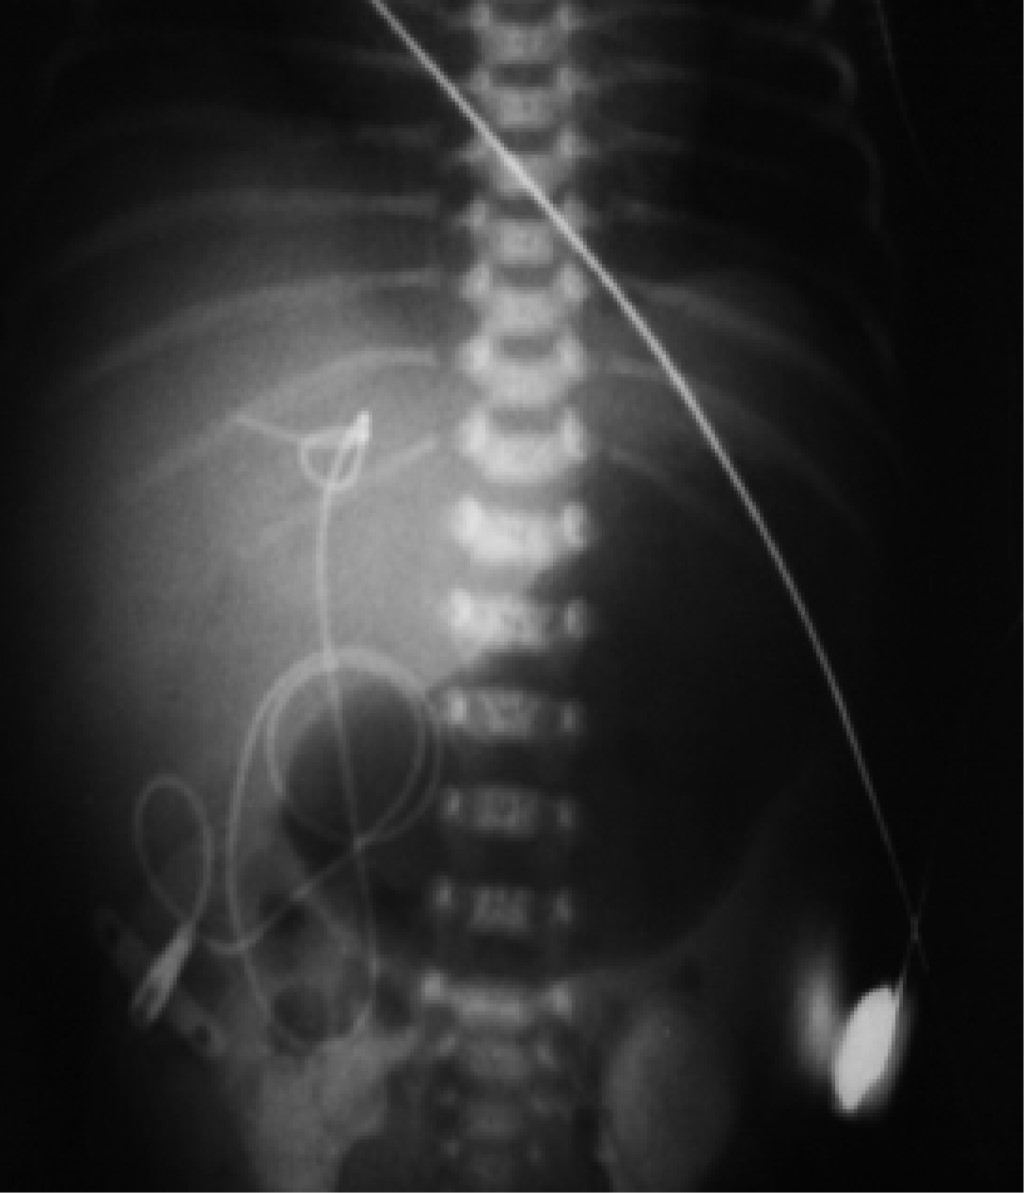

• 2. Se pueden diferenciar radiológicamente por su trayecto anatómico, el catéter venoso al entrar a pared abdominal se dirige hacia dirección cefálica y se sitúa en el lado derecho de abdomen y el arterial al entrar a pared abdominal se dirige hacia dirección podálica, de tal forma que baja para entrar a la arteria iliaca interna derecha o izquierda y hace un bucle para ascender por las iliacas y llegar a la arteria aorta, situándose ligeramente por el lado izquierdo del abdomen.

• 6. En una radiografía tangencial de abdomen y tórax, los catéteres tienen una distribución muy particular, el venoso se dirige siempre hacia dirección cefálica, hacia arriba por la pared abdominal anterior para pasar a un lado del hígado y llegar al corazón derecho. El catéter arterial se dirige siempre hacia dirección podálica, hacia abajo de la pared abdominal hasta alcanzar la arteria iliaca interna derecha o izquierda y de esta forma ascender para llegar a la arteria aorta, haciendo un bucle y correr por encima de los cuerpos vertebrales lumbares y dorsales (Figuras 12 y 13).